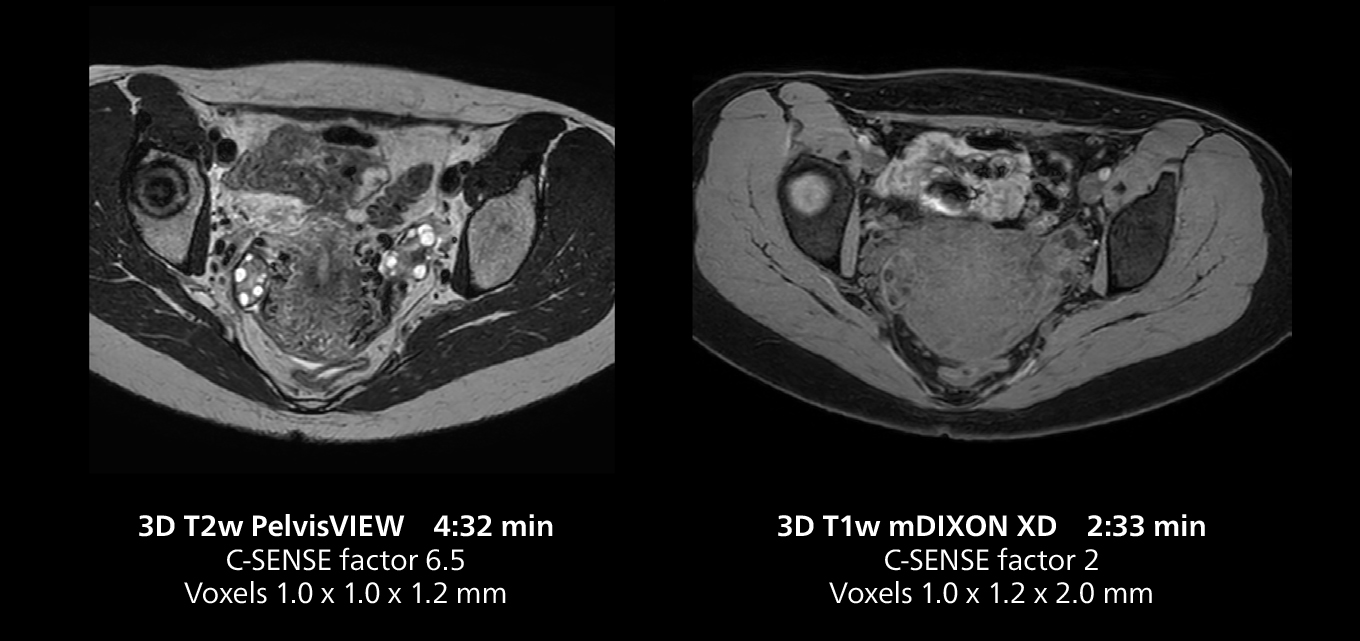

Dr. Gellée highlights the robust free-breathing scans as “the feature that makes the biggest difference in my daily work. The 3D free breathing sequences are very reproducible, and the axial acquisition is very good. For example, in endometriosis, which is one of my focus areas, it provides high contrast and good resolution so that I can see small details. We also use free breathing for liver and pancreas imaging. In multi-phase liver studies, 4D Free Breathing delivers 3-second temporal resolution, making a dynamic scan with more than one arterial phase possible.”

This MRI case illustrates good resolution and imaging quality obtained within reasonable scan times using the MR 5300 1.5T system with the anterior torso cardiac coil that allows use of a large field of view (FOV).